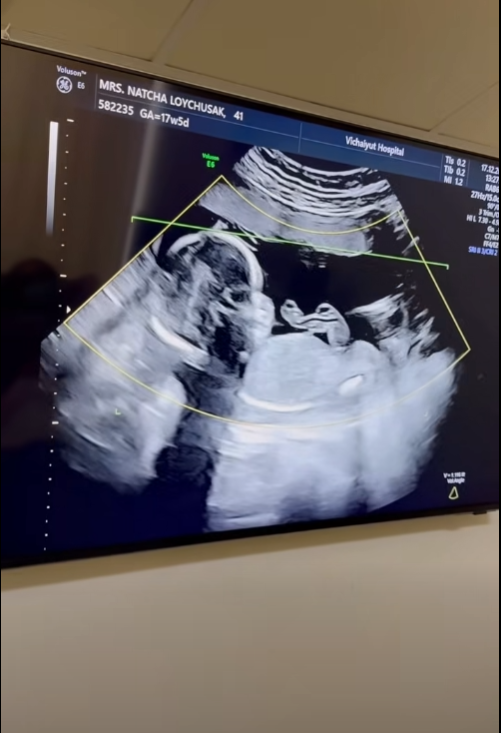

เรียกได้ว่าเป็นช่วงเวลาแห่งความสุขแบบคูณสองของครอบครัว “ลอยชูศักดิ์” เลยทีเดียว เมื่อคุณแม่คนสวยอย่าง “ครูก้อย นัชชา ลอยชูศักดิ์” ภรรยาสุดที่รักของ “เจมส์ เรืองศักดิ์ ลอยชูศักดิ์” ออกมาอัปเดตการตั้งครรภ์โชว์ท้องที่เริ่มป่องอย่างเห็นได้ชัด หลังตั้งครรภ์ลูกสาวคนที่สองได้ 17 สัปดาห์ พร้อมโชว์ภาพอัลตราซาวด์ที่เผยให้เห็นว่าเบบี๋ตัวยาวสมบูรณ์สุดๆ แถมมีแววจะตัวสูงตามรอยพี่สาวอย่าง “น้องเมดา” มาติดๆ